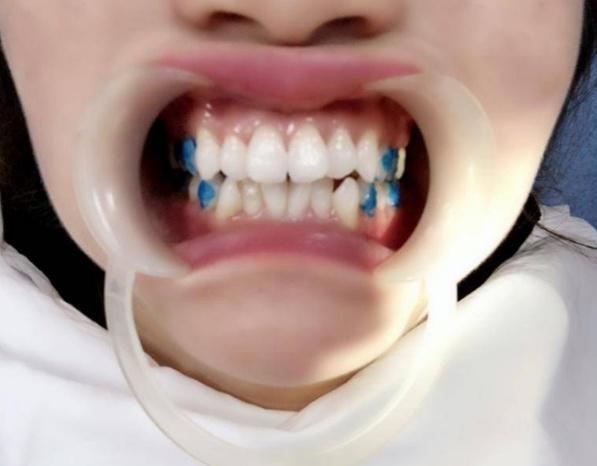

牙套做好后,医生给我做了片切,还粘了附件(就在上图涂蓝色的牙齿上面)。据说这些精细的工作非常考验医生的技术,我发现我的医生操作起来非常熟练。我的牙齿也没有觉得有啥敏感或不舒服的,全程都可以接受。